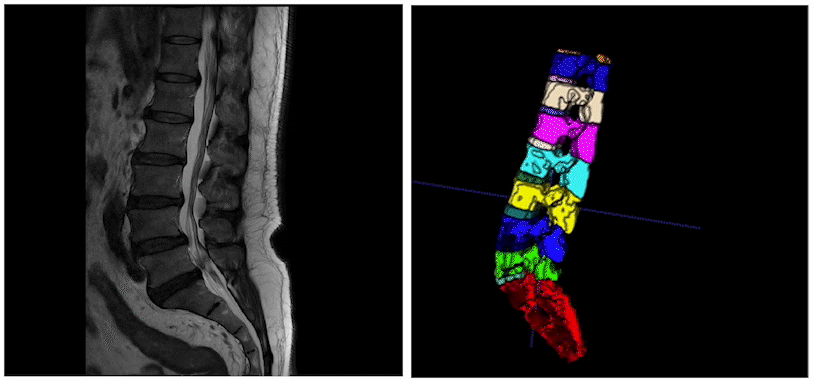

3D医疗影像分割通过学习3D医疗影像数据(CT、MRI)和特定标签的映射关系,获取3D的特定感兴趣器官、组织的立体分割结果。进一步结合3D打印、数据分析、可视化等技术,就可以帮助医生对患者的病情进行高效诊断、手术规划、疾病研究等重要工作。

多层2D椎骨数据通过3D分割获得3D立体分割结果

医疗影像分割中的一个源头性问题为数据标注极为困难,专业医生需要通过极为繁杂的标注流程、多重质量保证机制来生成大量、准确标注结果。为了缓解这个问题。PaddleSeg团队创新性地将3D网络应用于交互式分割流程中,并实现 100%3D数据流 ,形成了基于3D交互式分割的智能标注平台EISeg-Med3D。

EISeg-Med3D基于3D Slicer搭建,具有 高效 、 高精度 、 用户友好 三大特点:只要一次点击1s生成3D标注结果,相比2D标注实现十倍提速;两次点击就可达到85% 精度,结合搭载的机器学习图像算法、手工微调工具,实现 100%高精度 标注;拥有标注进度管理、三步轻松安装、历史标注结果自动导入等 用户友好 设计。